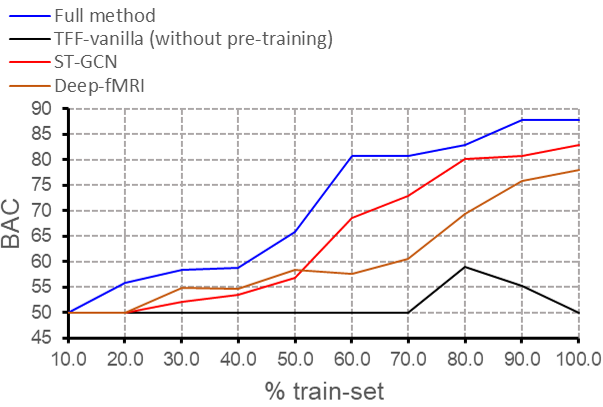

Variable Training Set Size We vary the amount of data available for training and evaluate the performance of each model for schizophrenia classification on the CNP dataset. The results, as shown in Fig. 8 in the appendix, indicate that the performance of all four methods drops significantly when the amount of training data is reduced. It is also evident that for all training set sizes the full TFF method is better than the baselines.

The results for comparing the convergence of TFF and TFF during the shared fine-tuning stage can be seen in Fig. 8. The results for the variable training set size experiment, from the main text, can be seen in Fig. 8.